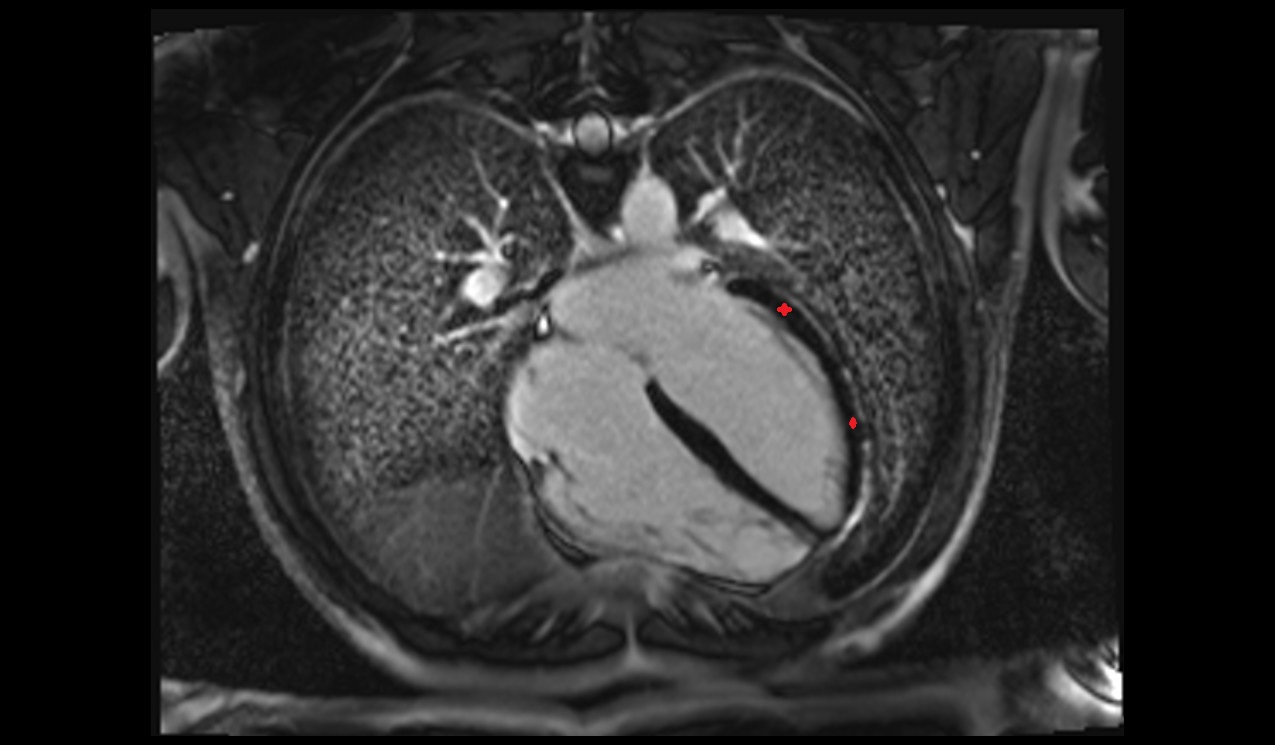

- Heart

- Left ventricle

- Left atrium